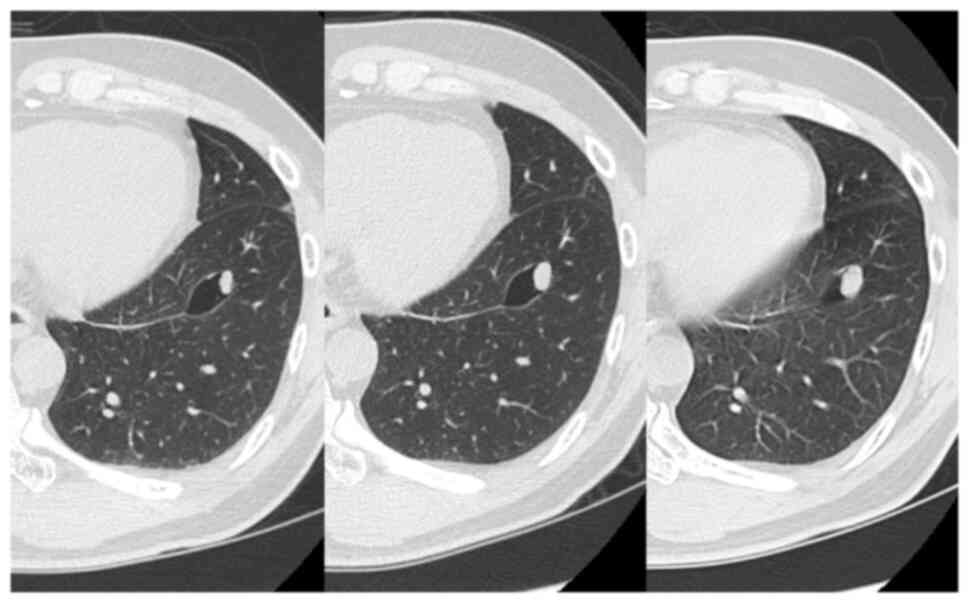

A 50-year-old male patient presented to his previous doctor with a complaint of chest discomfort. A chest computed tomography (CT) scan revealed a 10-mm solitary nodule with a single cyst in the left lower lobe. The diameter of the pulmonary nodule increased to 14 mm within a span of 2 years (CT scan results shown in Fig. 1). He was referred to Kansai Medical University Hospital (Hirakata, Japan) due to the possibility of lung cancer. His medical history was notable for benign prostatic hyperplasia. A thoracoscopic wedge resection of the left lower lung was performed. The frozen sections were non-diagnostic, and the surgical procedure and postoperative course were uneventful, with no signs of recurrence 4 years post-operatively.

Figure 1

Chest CT illustrating a well-defined nodule in segment 8 of the left lung with a surrounding vacuole, and the nodule increased in size on the CT scan for 2 years (images from left to right indicate the passing of time, respectively).